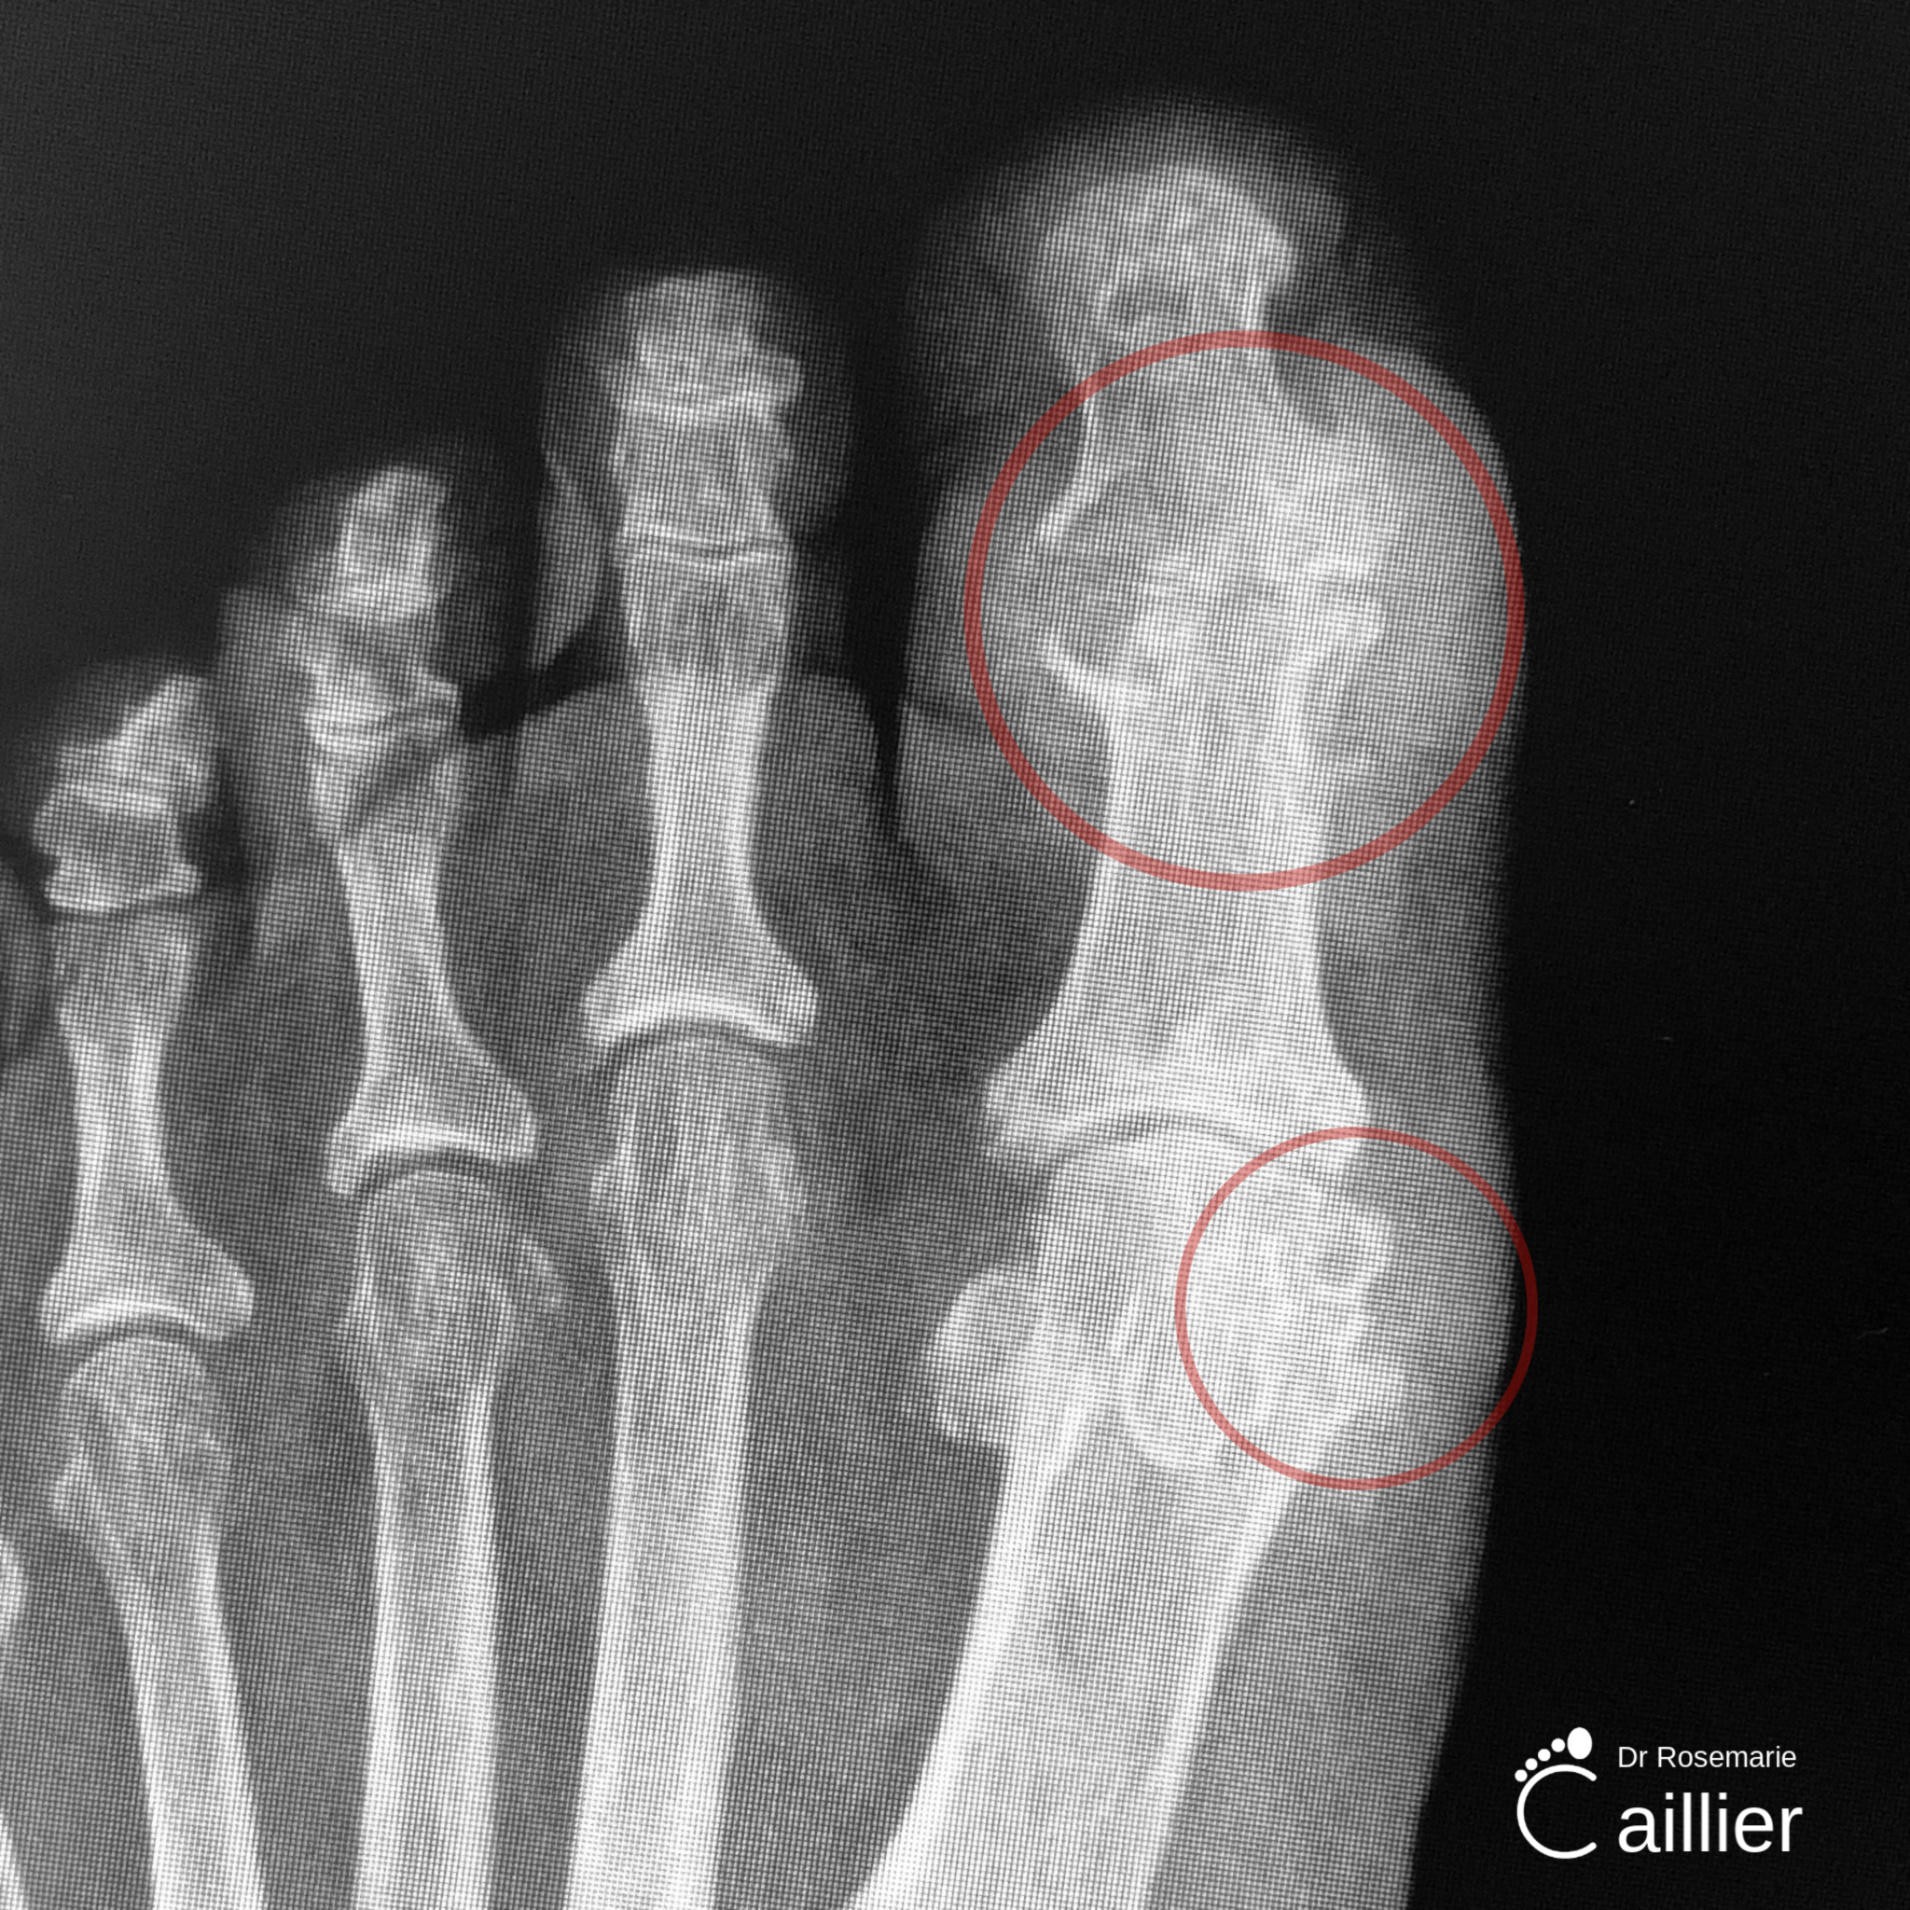

X-Ray Gout Image

Gout is a type of arthritis that can develop in the form of sharp crystals forming in the joints, usually that of the big toe. Flare ups are called “gout attacks,” which include pain, redness, and swelling, and the general feeling that the joint is on fire. Symptoms most commonly occur during the night.